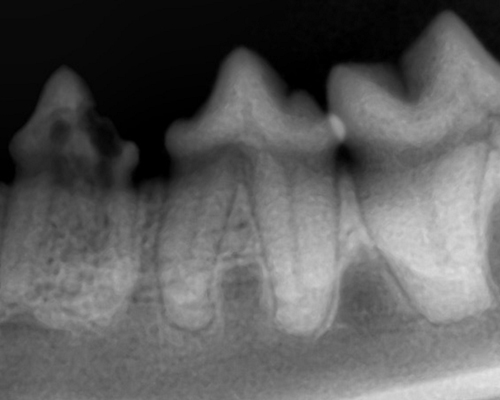

치아 방사선 촬영

- 치과 진료 시 가장 중요한 검사는 치아 방사선 촬영입니다.

우리가 눈으로 보는 치아 부위는 전체 치아의 일부이기 때문에 잔존 치아를 체크하기 위해서는 치아 방사선 검사가 반드시 진행되어야합니다.

4. 고양이 치아 흡수성 병변(Tooth Resorption)

- 원인이 정확히 밝혀지지는 않았으나 고양이에서 발생하는 치과질환 중 30%를 차지할 정도로 많으며 흔한 질환입니다. 치아 뿌리나 위쪽 부위가 점차 흡수되는 질환입니다.

- 특히 흡수가 진행될수록 통증이 심해지게 되며 삶의 질이 저하됩니다.

- 보호자가 육안으로는 관찰하기 어려운 경우가 많아 수의사의 진단이 필요합니다.

- 현재까지 치료 방법은 발치가 가장 추천됩니다.